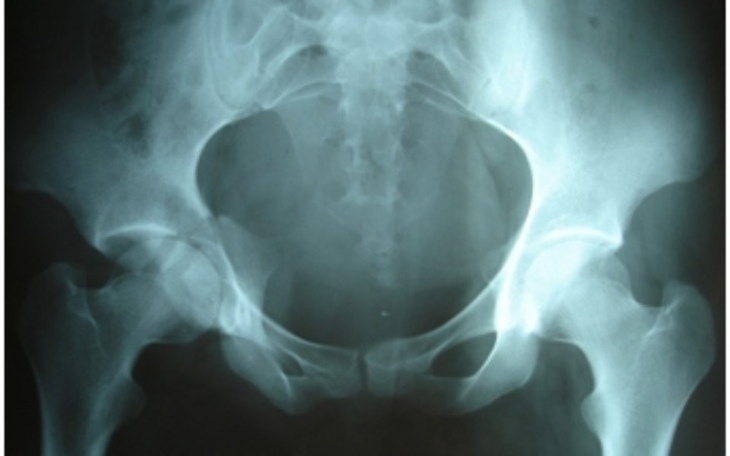

Witam. Wracając do Warszawy w piątek wieczorem zobaczylam na poboczu psa leżącego na ziemi. Wokół niego była krew. Zatrzymalam się i okazało się że pies żyje. Ktoś potrącił psa i nawet nie udzielił mu pomocny. Pies jest po operacji stracił niestety oko i ma złamaną miednice . Dostaje kroplowki przeciwbólowe i na wzmocnienie. Wiem że ten pies nie znajdzie już domu więc razem z synem postanowiliśmy że my stworzymy mu prawdziwy dom za to że ktoś to już skrzywdził . Nie miałam czasu na robienie zdjęć psa potraconego bo najważniejsze było mu pomóc jak najszybciej. Gdy tylko dojdzie do siebie to wstawię zdjęcia. Żeby zapłacić za leczenie brakuje mi kwoty 2500zl ( resztę kwoty udało mi się uzbierać) proszę dobrych ludzi o wsparcie finansowe